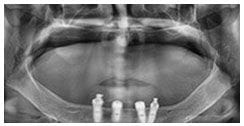

X 光片

術後X光片